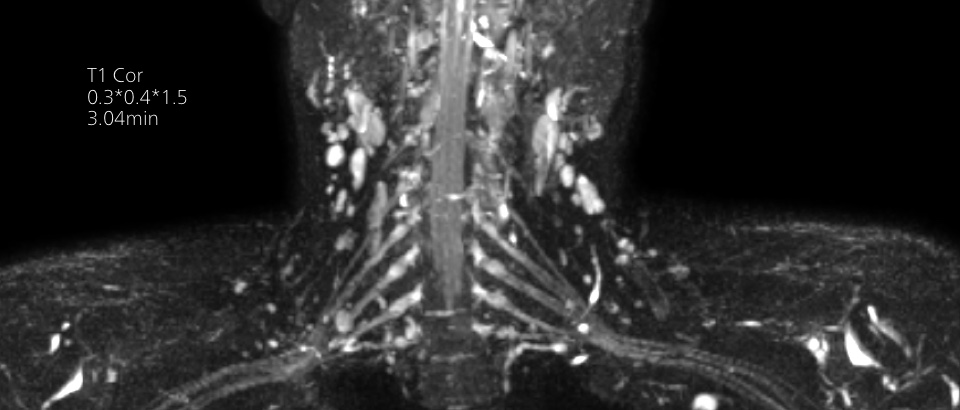

Philips Breezeコイルは、正確な解剖学的構造や非常に小さな関節を撮影するための優れた汎用性を備えています。最大55 cmの広い撮像視野と優れたSNRにより、高い画質が得られます。